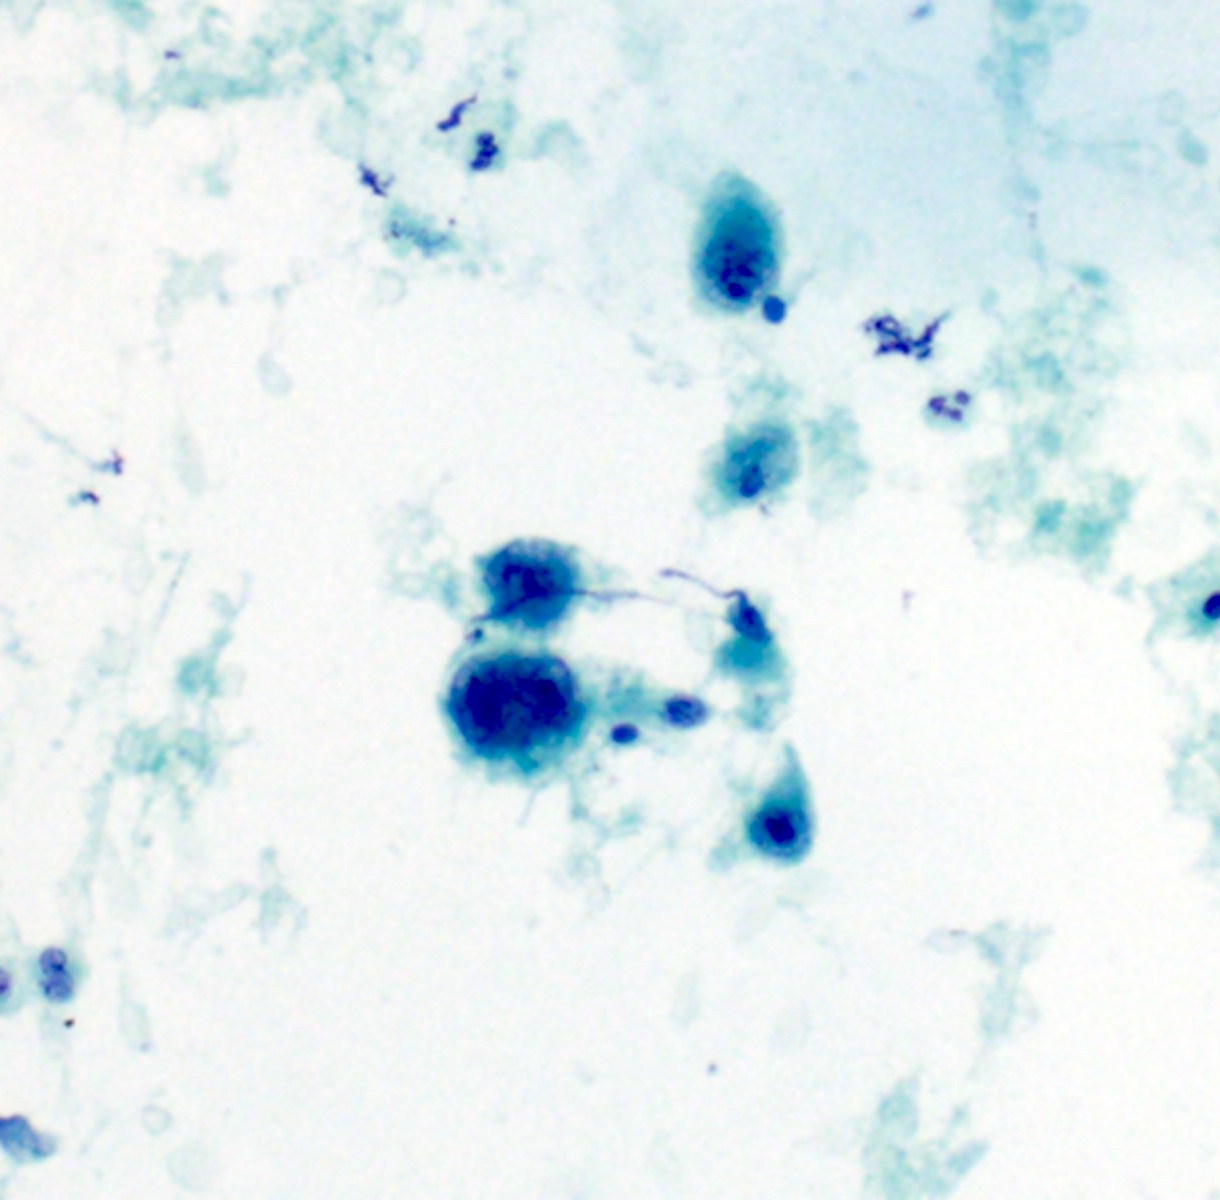

Cytology description

- Well differentiated tumors have elongated cells, isolated cells, tightly cohesive clusters or syncytia (Cibas: Cytology - Diagnostic Principles and Clinical Correlates, 4th Edition, 2014)

- Poorly differentiated: large spindle shaped or epithelioid shaped pleomorphic nuclei (Cibas: Cytology - Diagnostic Principles and Clinical Correlates, 4th Edition, 2014)

- Rhabdoid forms may occur in some epithelioid angiosarcomas (Cibas: Cytology - Diagnostic Principles and Clinical Correlates, 4th Edition, 2014)

- Discohesive epithelioid cells with nuclear pleomorphism and occasional spindle cells (Cibas: Cytology - Diagnostic Principles and Clinical Correlates, 4th Edition, 2014)

- Variably cellular with necrotic background (Cancer Cytopathol 2016;124:659)

- Dense cytoplasm with cytoplasmic vacuoles containing red blood cells (erythrophagocytosis) or neutrophils (Cancer Cytopathol 2016;124:659)

- Endothelial wrapping suggestive of vascular channel formation (Cancer Cytopathol 2016;124:659)

- Large, atypical round to oval nuclei with prominent bar shaped nucleoli (Cancer Cytopathol 2016;124:659)

- Multinucleated tumor giant cells with atypical mitotic figures (Cancer Cytopathol 2016;124:659)

Cytology images